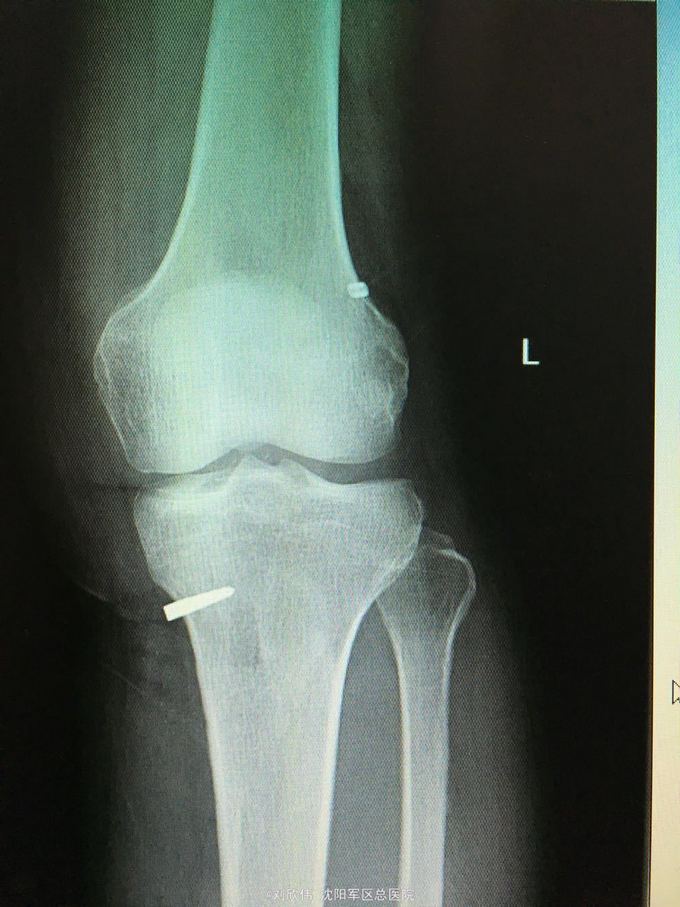

男性,44岁,摔伤所致,左膝。诊断如题

前抽屉,lachman,轴移阳性,外侧应力试验因疼痛无法进行

诊断如题,关节镜解决acl,mcl给予支具保守治疗

这个病例值得讨论的有2点,其一,mcl即内侧副韧带的处理通常可以保守治疗,二期不稳后再行手术治疗。第二,前叉胫骨侧隧道内口的位置,一个原则,宁内勿外。